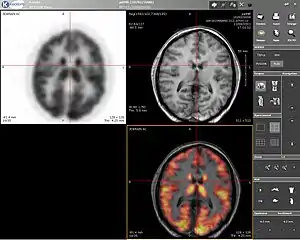

Computer screenshot showing a PET image (upper left), MRI image (upper right) and the combined PET-MRI image where PET data is overlaid over the MRI data (lower right) | |